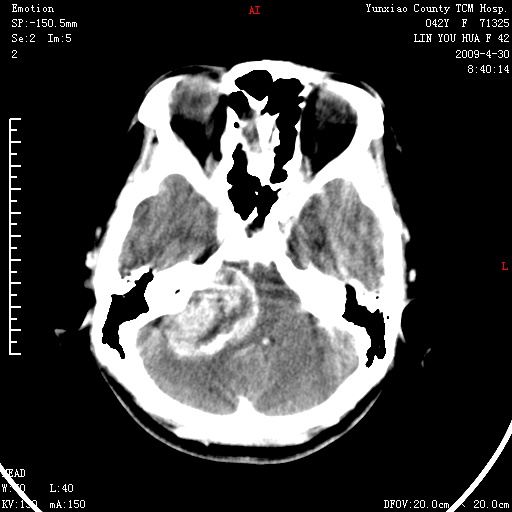

右侧桥小脑角区肿瘤,高密度囊变有显著强化,骨窗见内听道显著扩大,考虑听神经瘤可能性大

1)右侧听神经瘤。2)阻塞性脑积水。

内听道扩大,支持考虑听神经瘤可能性大。